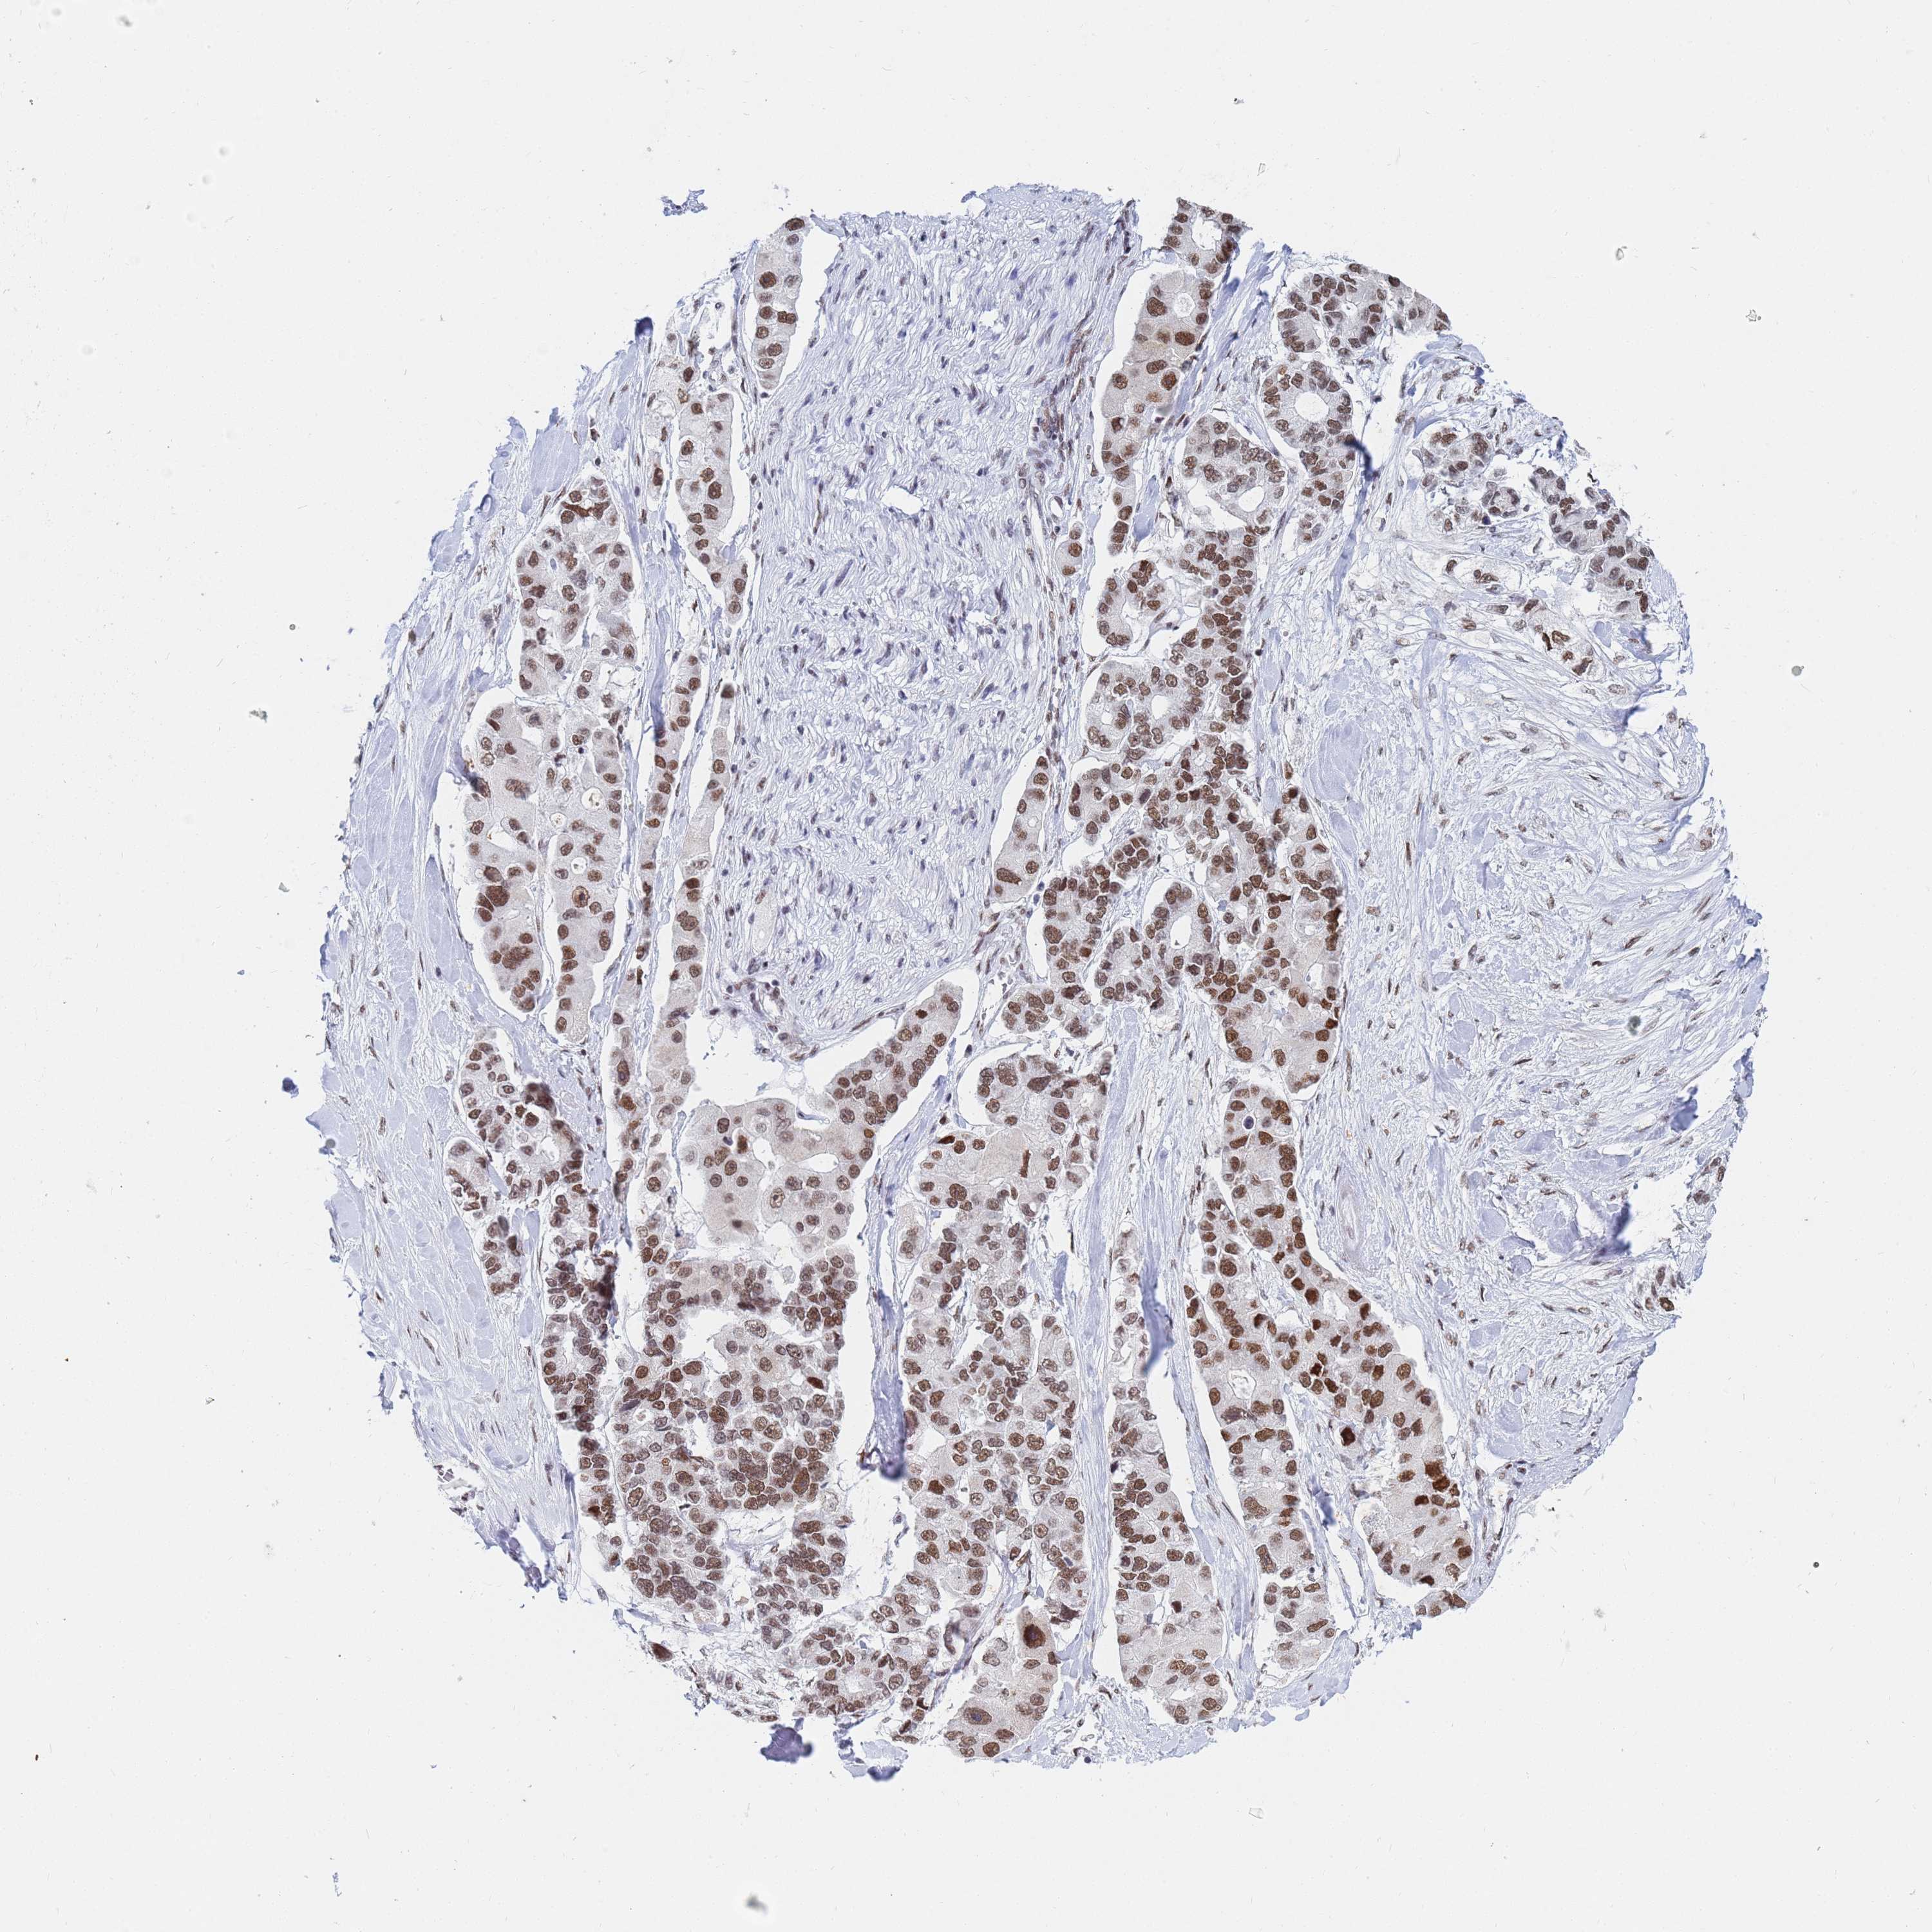

CANCER LUNG CANCER Show tissue menu